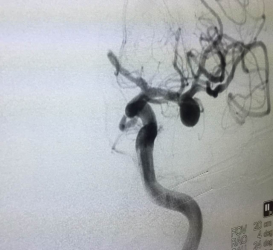

病例一:患者周先生39岁,突发头痛伴恶心、呕吐6小时,永州市中心医院神经外科治疗,头颅CT检查显示为“蛛网膜下腔出血”,立即行头颅CTA检查显示为“左侧大脑中动脉瘤”。主治医生林医生请示上级医师指导,结合病史、体查及辅查,诊断为:1.自发性蛛网膜下腔出血;2.左侧大脑中动脉瘤破裂;3.高血压病 2级 。予完善相关检查,与患者家属沟通后立即制定周密的手术方案,行全脑血管造影术+左侧大脑中动脉M1段动脉瘤介入栓塞术,手术结束后再次造影显示动脉瘤致密栓塞,载瘤动脉完好。术后患者病情稳定,正在恢复期中。

例二:患者黄某,女,54岁,头晕头痛一月入住市中心医院神经内科,完善相关检查后考虑海绵状血管瘤,请会诊转入神经外科手术治疗。行血管造影术后确诊为右侧颈内动脉床突段动脉瘤,并立即行支架辅助弹簧圈,手术顺利。患者术后三天后可下床走动,术后五天再次复查结果显示良好,现已康复出院。

周先生术前结果                      周先生术后结果

黄女士术前显影                     黄女士术后显影